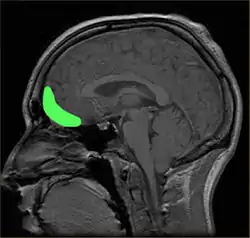

Although the precise neural mechanisms underlying disorders of impulse control are not fully known, the prefrontal cortex (PFC) is the brain region most ubiquitously implicated in impulsivity.[142] Damage to the prefrontal cortex has been associated with difficulties preparing to act, switching between response alternatives, and inhibiting inappropriate responses.[136] Recent research has uncovered additional regions of interest, as well as highlighted particular subregions of the PFC, that can be tied to performance in specific behavioral tasks.